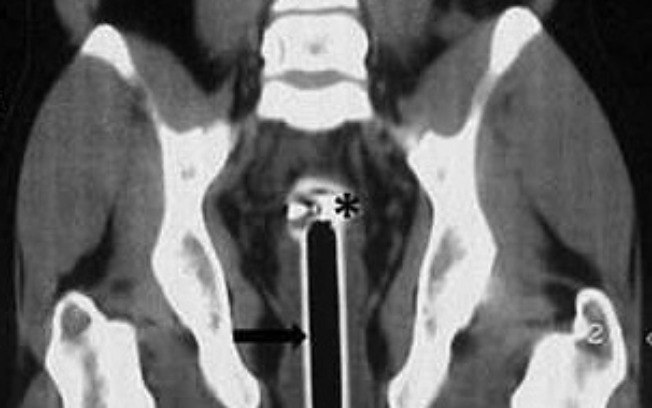

Rio – Um homem foi parar no hospital após um chuveirinho de 15 centímetros ficar preso em seu reto. O rapaz de 26 anos, que não teve a identidade divulgada, disse aos médicos que caiu em cima do objeto durante o banho em sua casa, na Índia, e que resolveu procurar ajuda após tentar retirá-lo sozinho e não ser bem-sucedido.

A equipe contou que o indiano ficou com a cabeça do chuveiro auxiliar e uma parte da tubulação presas no reto, e que reclamou de dores na região. Exames foram executados para avaliar o caso, e o rapaz está saudável, sem apresentar sangramentos internos.

O paciente passou por um longo processo de cirurgia, tendo o objeto retirado do ânus. Os médicos expuseram que mais exames tiveram de ser realizados para verificar se algum dano havia sido causado ao intestino grosso do rapaz.